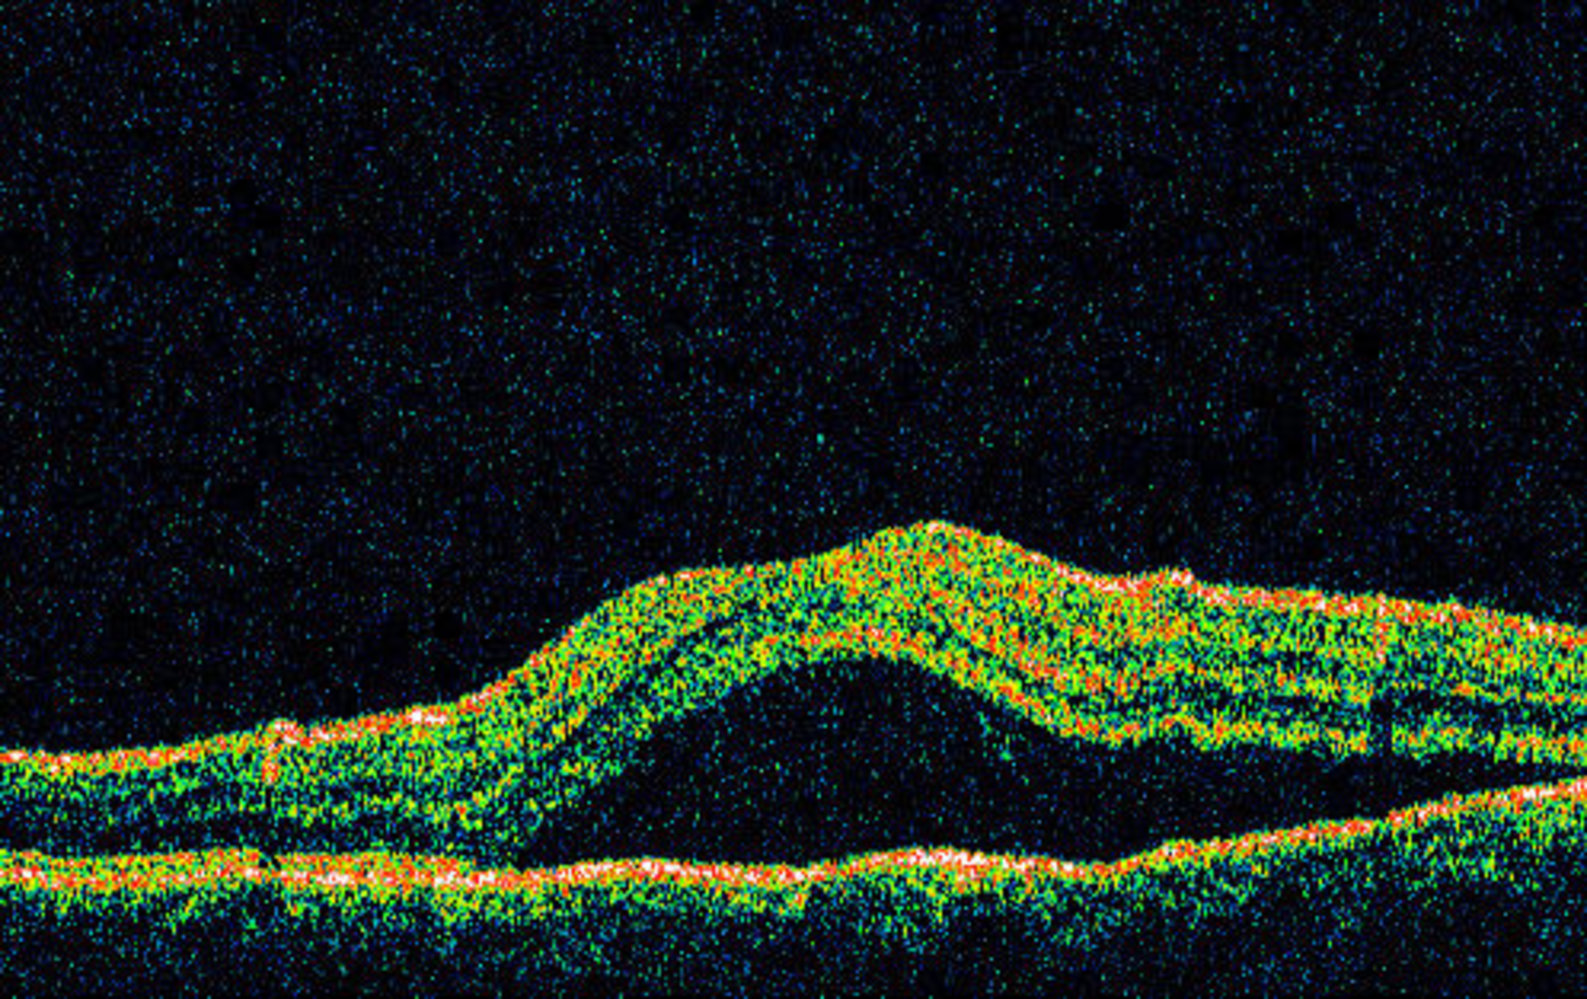

Central serous retinopathy (central serous chorioretinopathy)

• Definition: serous retinal detachment at the posterior pole of the eyeball (at the macula or in the perimacular region) due to a defect in the pigment epithelium

• Pathophysiology: defect in the area of Bruch's membrane/pigment epithelium β†’ fluid leakage from the sclera into the subretinal space β†’ serous retinal detachment

• Etiology

• Unknown

• Glucocorticoids and an increase in the diastolic blood pressure are possible risk factors.

• Stress-related

• Epidemiology

• Mostly affects men 20–45 years of age

• Clinical features

• Hyperopia

• Metamorphopsia (distorted vision)

• Patients perceive images as smaller than they are

• Relative scotoma (perception of a gray area or shadow in the central field of vision)

• Diagnostics

• Ophthalmoscopy: roundish detachment of the central retina

• Fluorescein angiography

• Optical coherence tomography (OCT)

• Treatment

• Often heals spontaneously

• Stress reduction

• Rarely: laser coagulation (in extramacular localization), photodynamic therapy